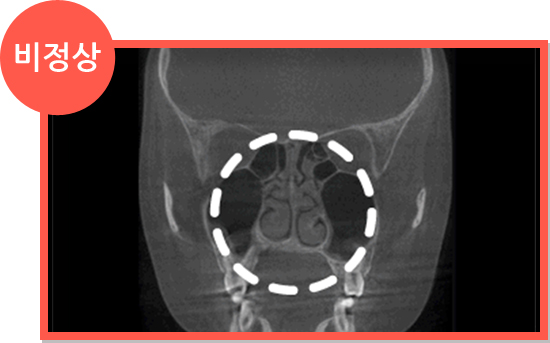

비염 CT 정상 소견 비염 CT 비정상 소견

• 만성비후성 비염

코덧살이 부어오른 만성비후성비염은 고주파를 이용한 간단한 수술이 필요합니다.